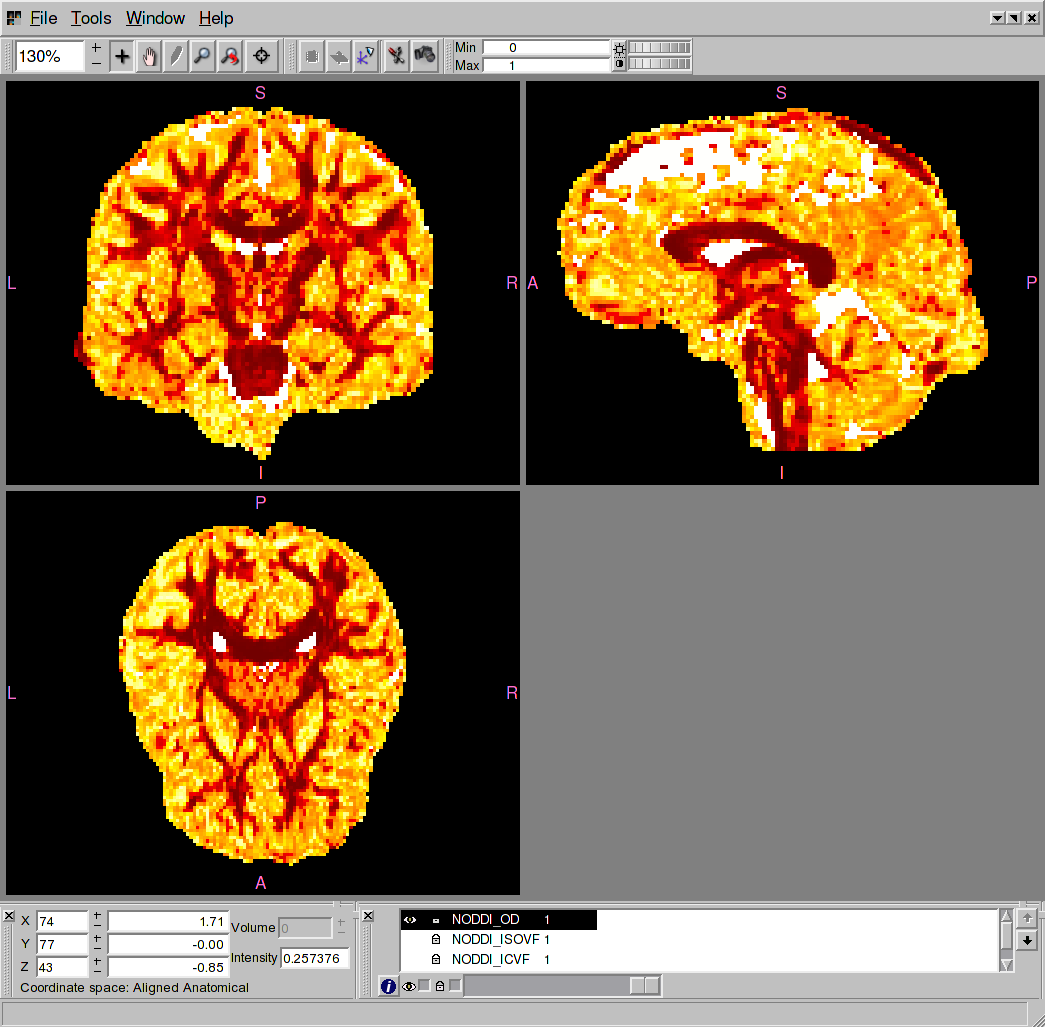

DWI images